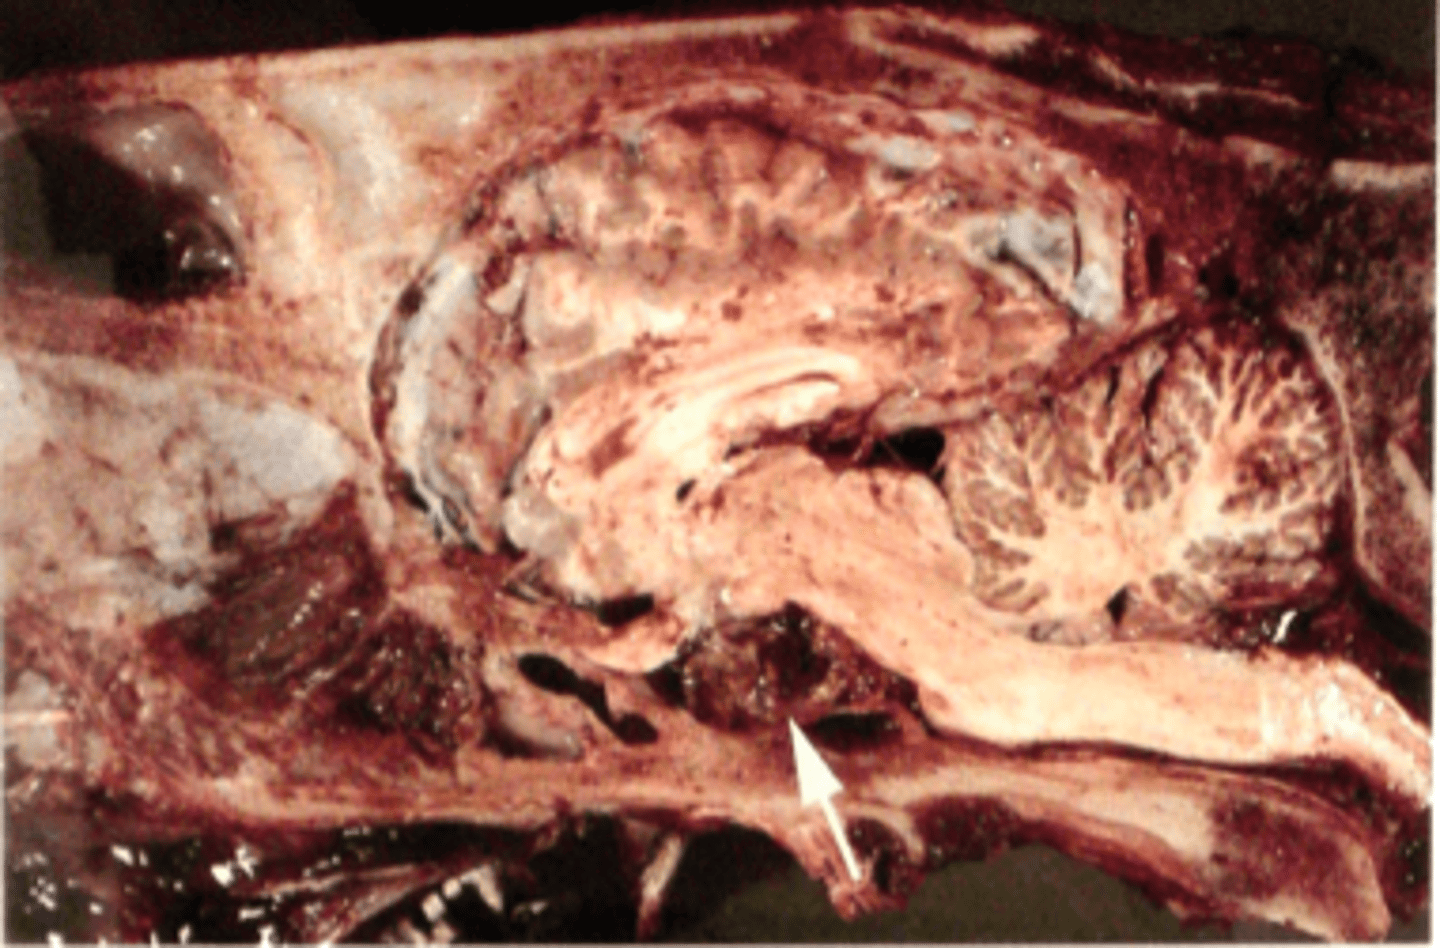

Benign hypofyseneoplasi med hæmorrhagi

Hovede fra hest, hvad er den patoanatomiske diagnose? Se pilen

Benign hypofyseneoplasi

Hypofyse fra hest, hvad er den patoanatomiske diagnose? Se pilen